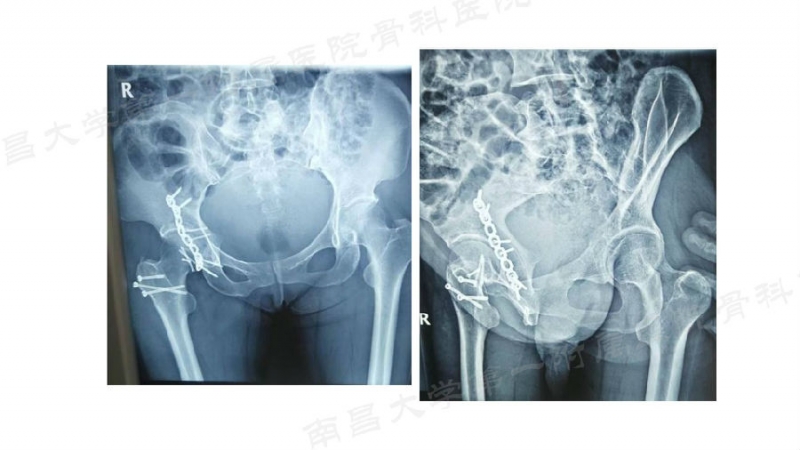

病例一

病例二

病例三